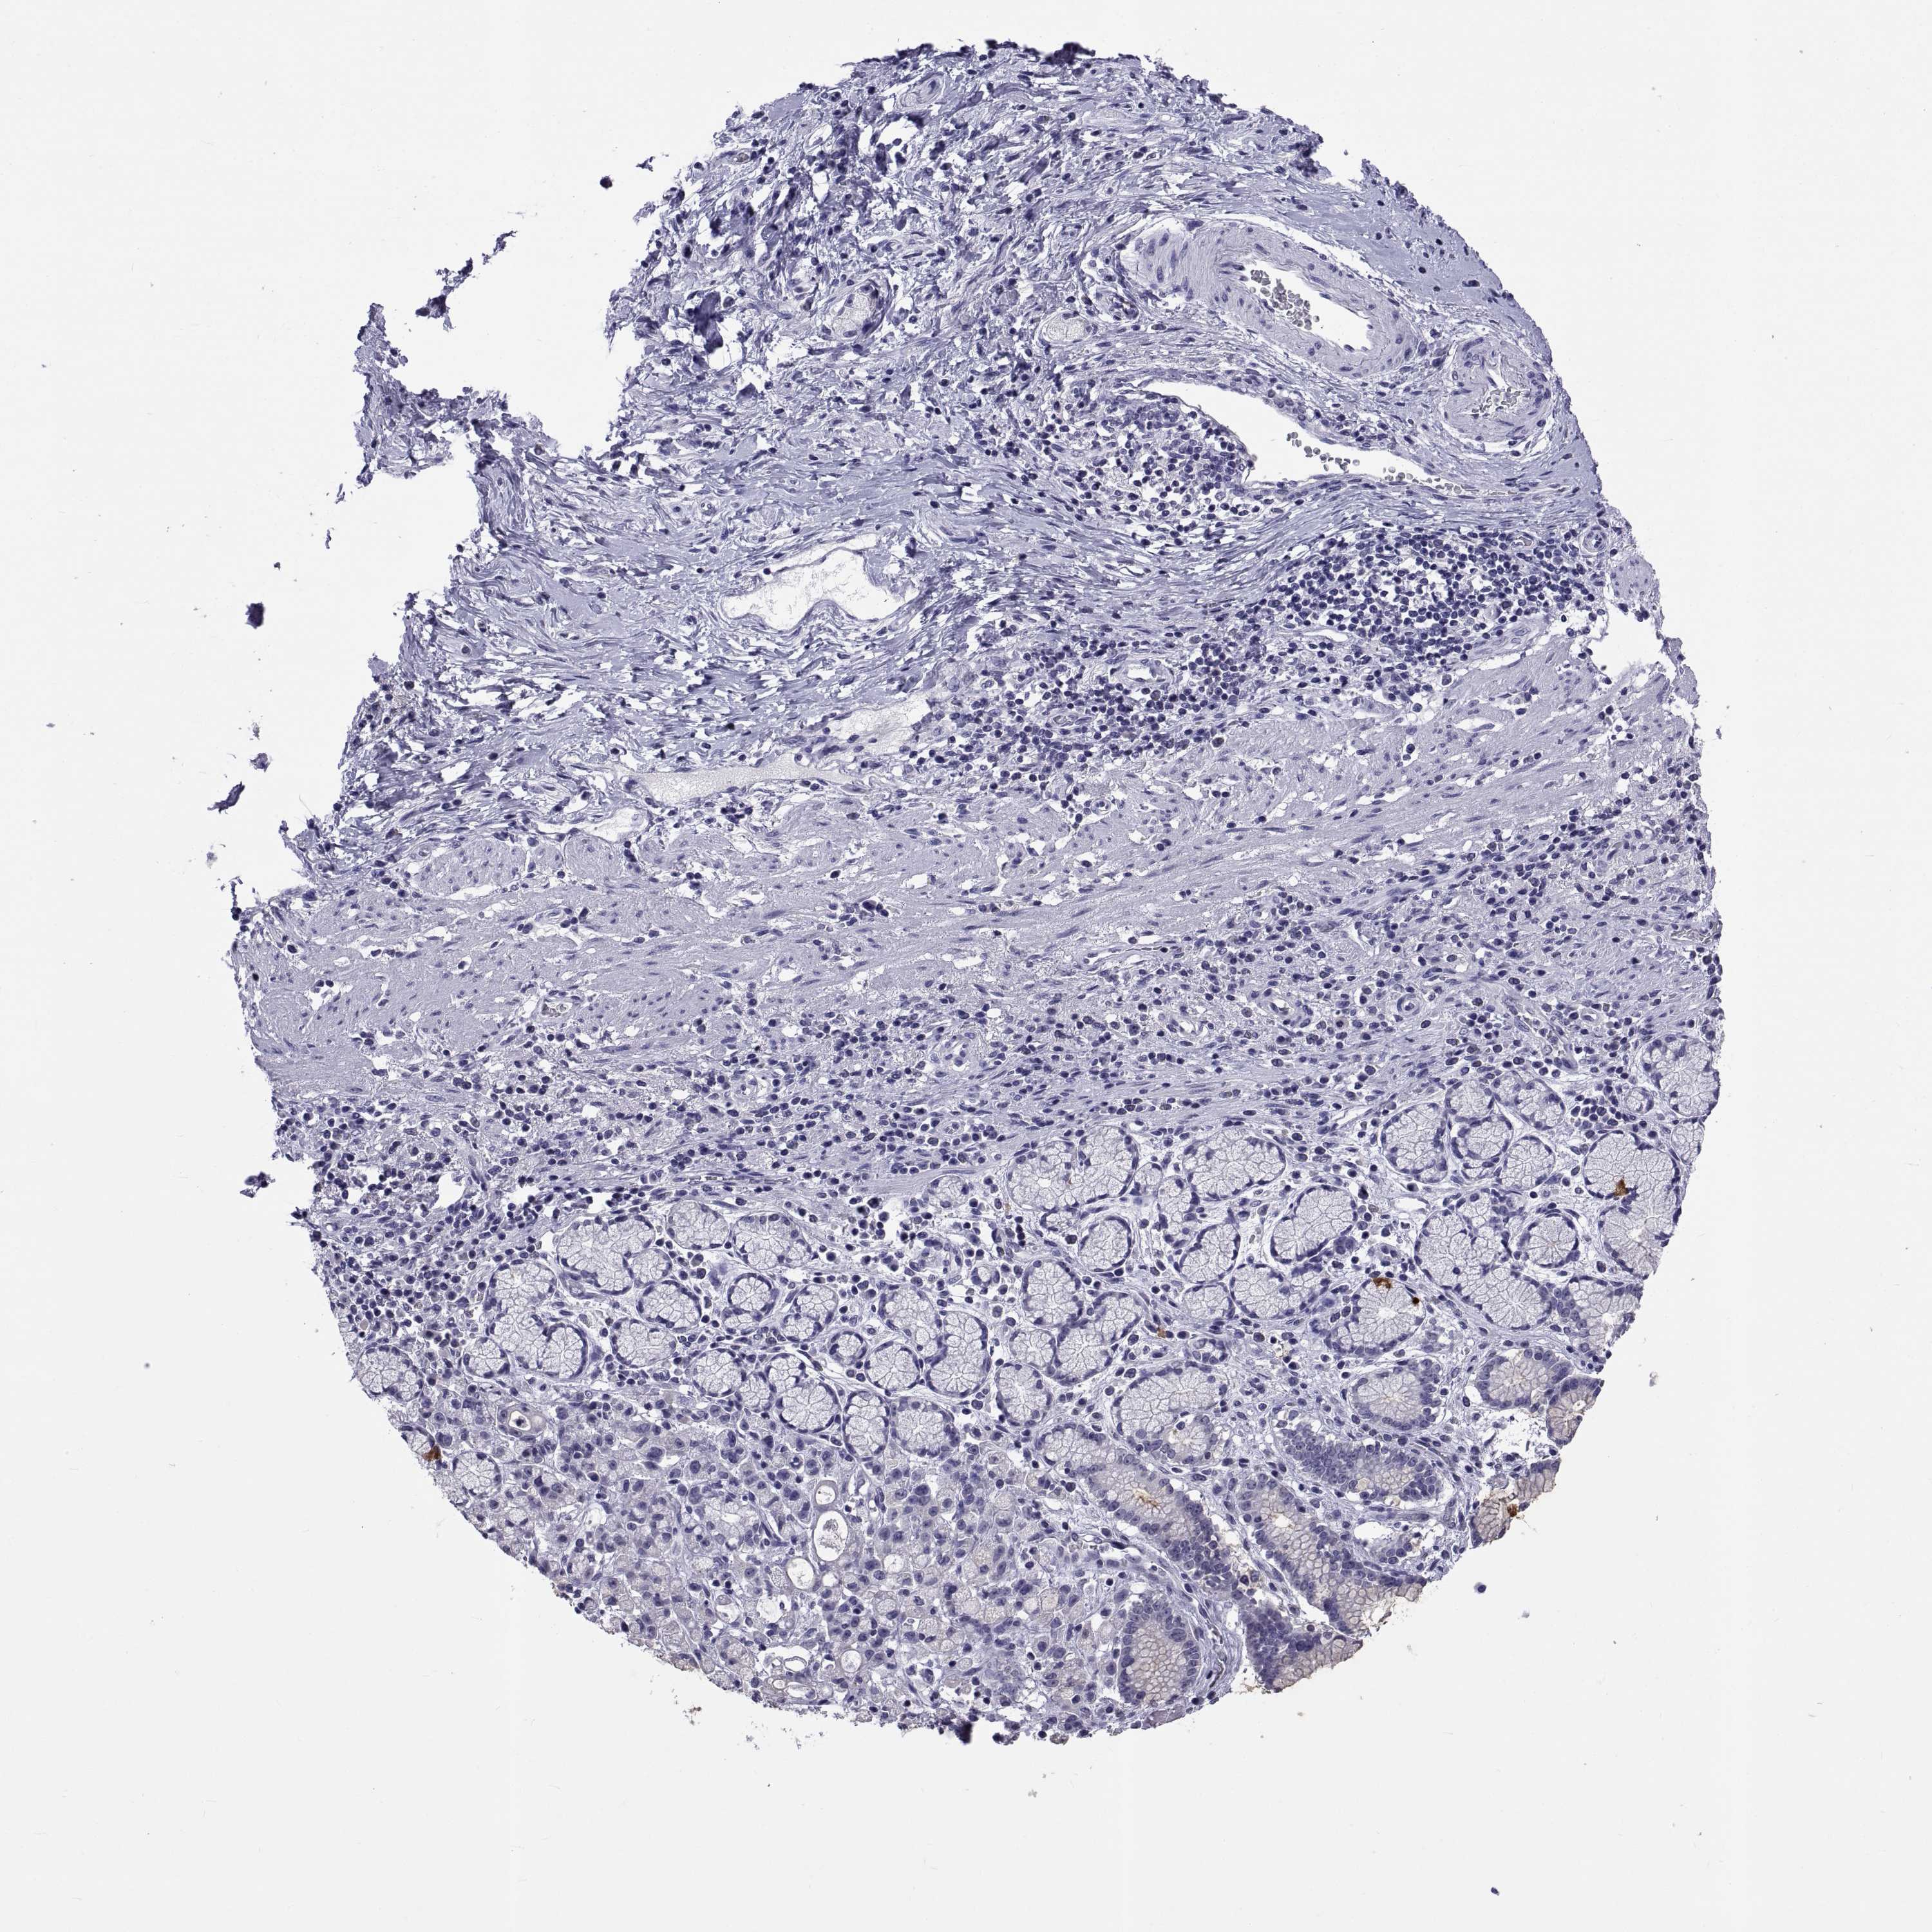

STOMACH CANCER - Protein expressioni

A mouse-over function shows sample information and annotation data. Click on an image to view it in a full screen mode. Samples can be filtered based on level of antibody staining by selecting one or several of the following categories: high, medium, low and not detected. The assay and annotation is described here.

Note that samples used for immunohistochemistry by the Human Protein Atlas do not correspond to samples in the TCGA dataset.

Antibody stainingi

Antibody staining in the annotated cell types in the current human tissue is reported as not detected, low, medium, or high, based on conventional immunohistochemistry profiling in selected tissues. This score is based on the combination of the staining intensity and fraction of stained cells.

Each image is clickable and will lead to virtual microscopy that enables deeper exploration of all samples and also displays staining intensity scores, fraction scores and subcellular localization as well as patient and tissue information for each sample.

Antibody HPA074356

Staining

High

Medium

Low

Not detected

Intensity

Strong

Moderate

Weak

Negative

Quantity

>75%

75%-25%

<25%

None

Location

Nuclear

Cytoplasmic/membranous

Cytoplasmic/membranous,nuclear

Adenocarcinoma, NOS

Adenocarcinoma, High grade